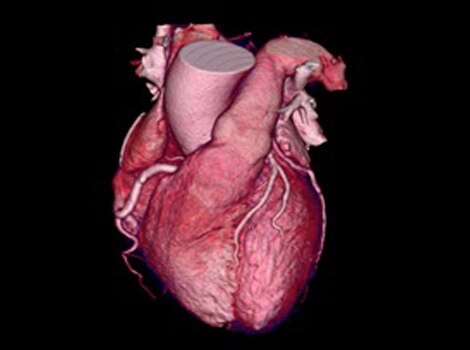

Revolution™ CT & CardioGraphe4

Achieve one-beat, whole heart acquisition for imaging or comprehensive cardiac assessment with or without beta blockers at any heart rate.5

Revolution™ CT & CardioGraphe7

Achieve one-beat, whole heart acquisition for imaging or comprehensive cardiac assessment with or without beta blockers at any heart rate.8

Revolution™ CT & CardioGraphe3

Achieve one-beat, whole heart acquisition for imaging or comprehensive cardiac assessment with or without beta blockers at any heart rate.4